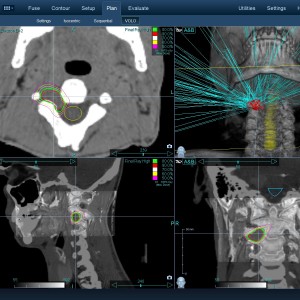

Στις παρακάτω φωτογραφίες θα δείτε παραδείγματα πλάνων θεραπείας καρκινικών όγκων με CyberKnife. Παρατηρήστε πόσο κοντά στους υγιείς ιστούς βρίσκονται οι καρκινικοί όγκοι που χρειάζεται να ακτινοβοληθούν. Μόνο με το CyberKnife και το προσωπικό πλάνο θεραπείας, μπορούν να ακτινοβοληθούν οι όγκοι χωρίς να πληγούν οι παρακείμενοι υγιείς ιστοί.

Με κόκκινο χρώμα περιγράφεται η περιοχή του όγκου.

Με μπλε, κίτρινο και πράσινο χρώμα περιγράφονται οι υγιείς ιστοί που δεν πρέπει να ακτινοβοληθούν.

Παρατηρήστε πόσο κοντά βρίσκεται ο όγκος με τους υγιείς ιστούς.

Παρατηρήστε τις πάρα πολλές δέσμες του CynerKnife που ακτινοβολούν τους όγκους από διαφορετικές γωνίες ώστε να μην προσβληθούν από την ακτινοβολία οι υγιείς ιστούς.